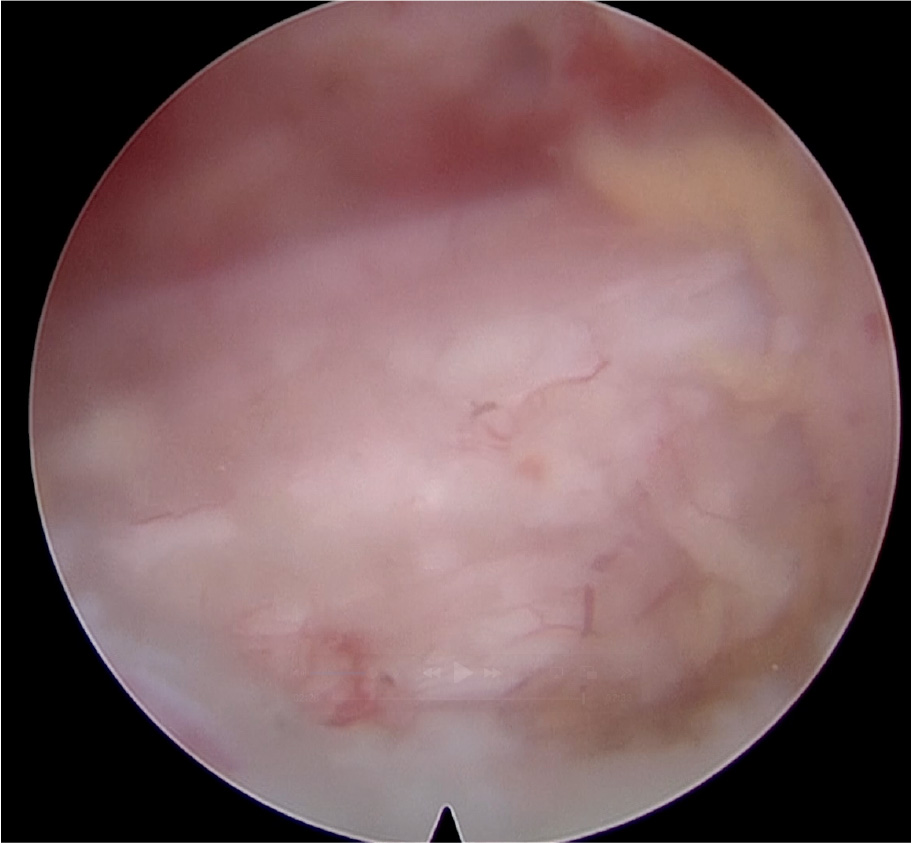

術後MRI:厚くなった靱帯や骨が切除され、

脊柱管が広くなっています(丸印)。

術中写真: